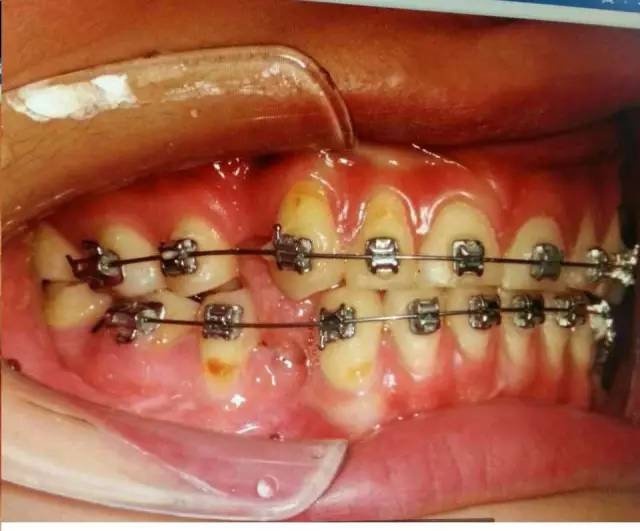

中醫(yī)有云“未病先防”,權(quán)老師發(fā)現(xiàn)患者舌位置的異常,檢查患者的吞咽方式,驗證其為嬰兒式吞咽。而舌在嬰兒式吞咽甚至是整個口頜系統(tǒng)中的作用是不可小覷的。嬰兒式吞咽舌頭抵在下牙,吞咽時會對牙齒產(chǎn)生向外的推力,應(yīng)力集中在頸部,導(dǎo)致牙齒微折裂,甚至出現(xiàn)牙齦萎縮、楔缺、牙根暴露,引起牙的冷熱痛。臨床上會發(fā)現(xiàn)一些前牙開(牙合)的病人前牙依然受到創(chuàng)傷,沒錯,依然是舌頭惹的禍。這也可以推測照片中患者13,43,45牙齦萎縮和頸部楔狀缺損與舌有關(guān)。

考慮到舌會對前牙有較大的沖擊力,甚至可能引起牙齒松動,權(quán)老師希望患者重視舌的問題,并引導(dǎo)患者嘗試改變吞咽方式。這樣全面的為患者考慮,發(fā)現(xiàn)問題,未病先防,深入一些,您也可以做得到。

患者牙齒出現(xiàn)的癥狀是矯治,側(cè)方干擾,以及舌的推力等因素疊加所致